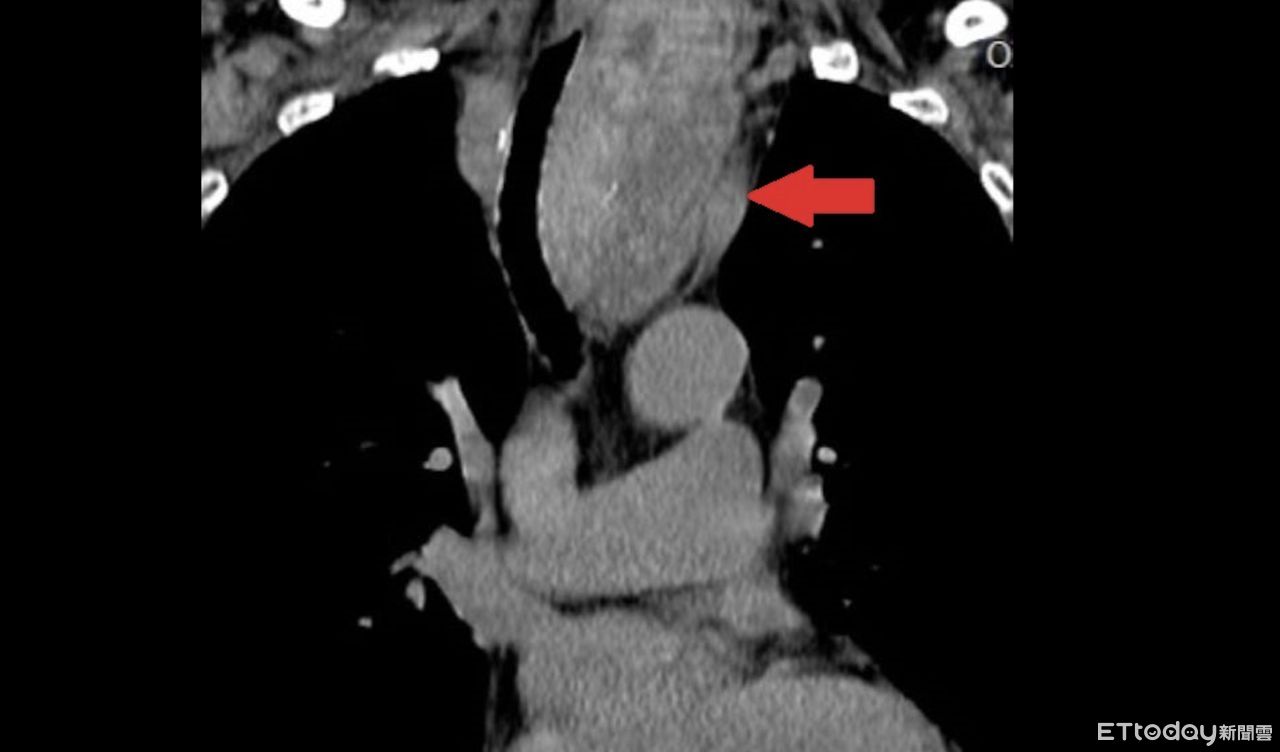

▲黃女士甲狀腺結節如芭樂大,已經擠壓氣管。(圖/醫師提供)

74歲黃女士10年前因右側甲狀腺結節問題,在醫院接受手術切除,3年前又發現左側結節逐漸增大,出現吞嚥困難、頸部腫脹,再度檢查發現結節已經侵犯胸腔,氣管已經被13公分如「芭樂般大」的結節壓迫偏移至右側,進一步安排手術切除。

收治該病例的台北慈濟醫院胸腔外科醫師洪嘉聰指出,黃女士左側結節切片數次均屬良性,原本想說在未影響生活的情況下,選擇持續觀察,但之後因出現不適症狀,檢查發現已經擠壓氣管,雖呼吸未受影響,但仍評估手術切除。